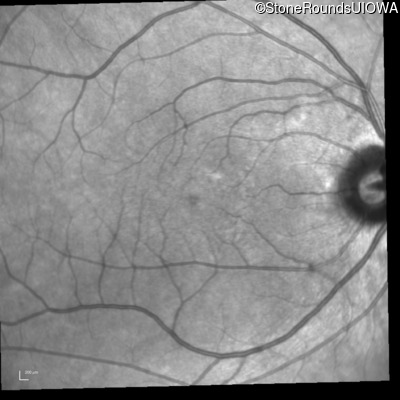

Infrared Fundus Photograph - Left - 20/20 -2

Exemplar